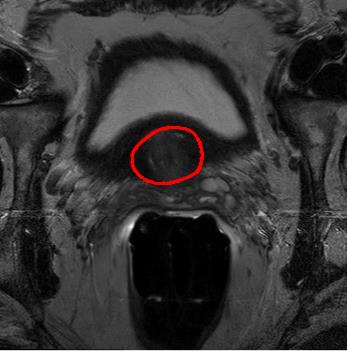

We trained our network on 77 patients. The input images and the manual ground truth annotation are shown in Fig.4. As we have described above, these images were acquired from different patients, and these images include the clinical variability. To evaluate our method, we randomly selected 4 patients with 64 images before training. These images do not take part in training and the prostate has been manually pre-delineated by a radiologist, which were used as the ground truth to evaluate the performance of automatic segmentation. We also selected dice coefficient as the evaluation method[30]. And to validate our method against U-Net and fully convolutional networks (FCNs), we used the same dataset to train and test the U-Net and FCNs.

To intuitively compare the proposed method with U-Net and FCN, the segmentation results of some representative and challenging samples are shown in Fig 5. It can be seen that these prostate images have fuzzy boundaries and the pixel intensity distributions are inhomogeneous both inside and outside of the prostate. Besides, both prostate and nonprostate regions have similar contrast and intensity distributions. All of these phenomenons make the segmentation difficult.